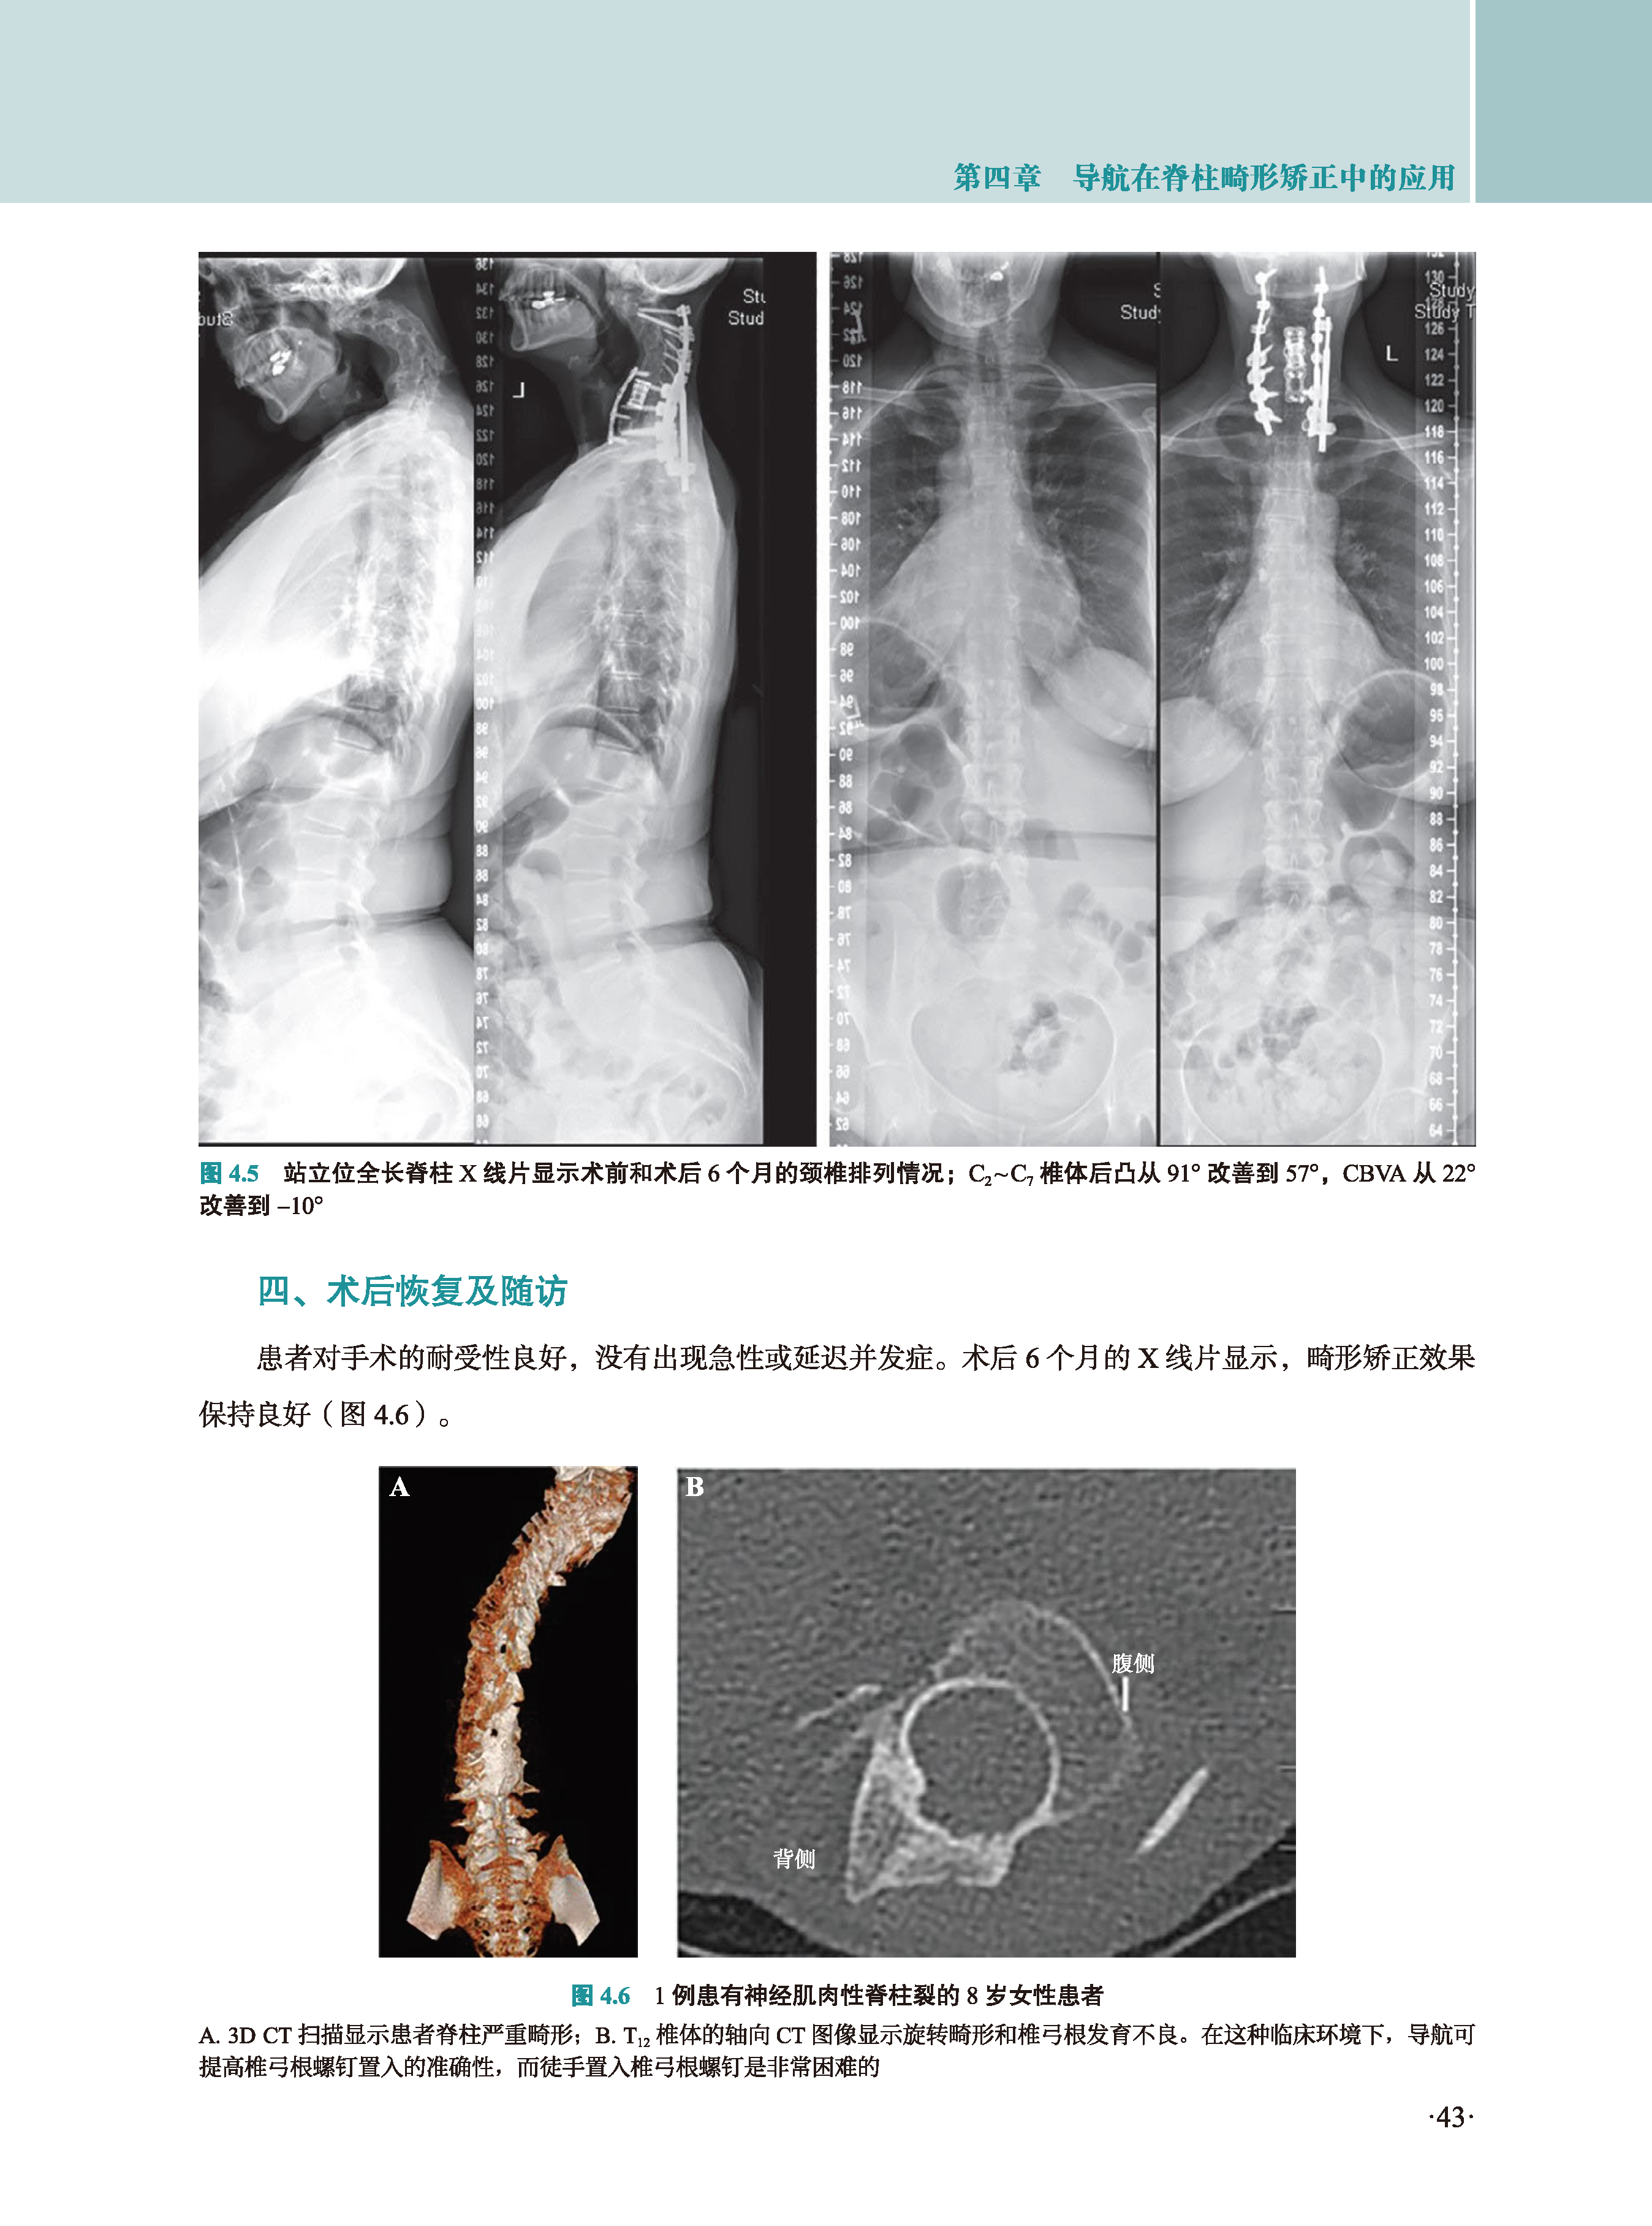

书中详细阐述了计算机辅助脊柱手术的多种形式,如远程机器人手术、共享控制机器人和计算机导航等。通过各章节对不同脊柱手术的介绍,包括枕骨和颈椎手术、脊柱创伤手术、脊柱畸形矫正手术等,展示了机器人和导航技术在各类复杂病例中的实际应用效果。同时,对手术相关的并发症、潜在隐患以及成本效益等方面也进行了深入分析,并对未来技术的发展方向做出了前瞻性展望。理论与实践相结合,为脊柱外科医生、医学生以及相关研究人员提供了极具价值的参考资料,有助于推动脊柱外科领域的技术进步和临床实践发展。